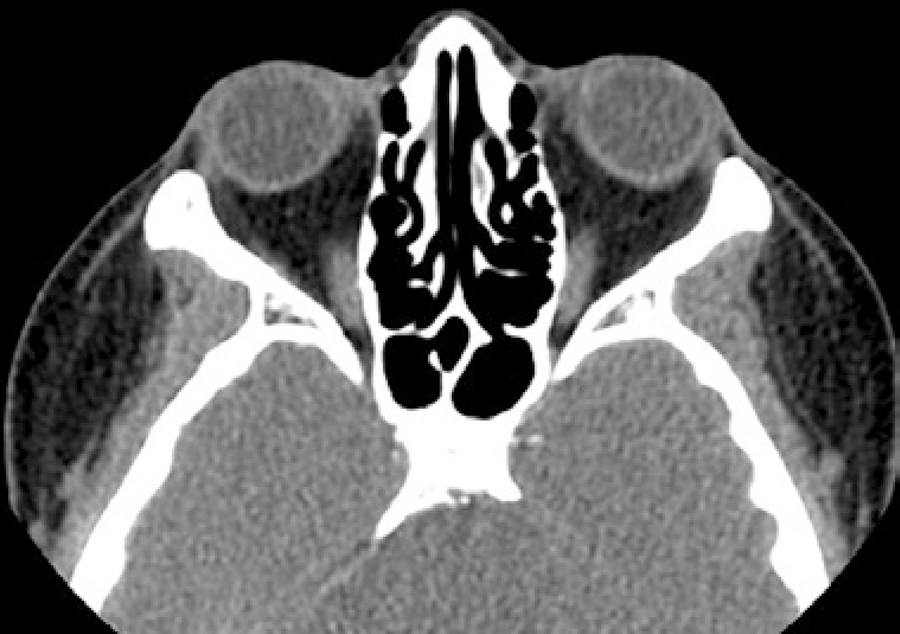

The patient was treated for posterior scleritis with oral prednisolone 1 mg/kg body weight once daily. After 2 weeks of treatment, an improvement in pain was noted by the patient, along with BCVA of 6/60 in the left eye with improvement of the macular OCT edema; however, on fundoscopy, worsening of the optic disc edema was found. The orbital CT scan and B-scan ultrasonography revealed identical results. Etiological investigation showed negative anti-HIV antibody test, C-reactive protein level of 0.3 mg/dL, elevated sedimentation rate (59 mm), negative rapid plasma reagin and treponema pallidum hemagglutination test, normal angiotensin-converting enzyme (25 UI/L), negative cytoplasmic and perinuclear anti-neutrophil cytoplasmic antibodies, negative Borrelia burgdorferi and Toxoplasma gondii IgG and IgM, and negative rheumatoid factor and antinuclear antibodies. The chest radiograph was normal and the patient denied any respiratory symptoms or recent travel in TB-endemic regions. The patient had a positive result for the purified protein derivative (PPD) skin test (17 mm induration under corticotherapy 80 mg/day) and interferon-gamma release assay (IGRA), which is a more specific test. Antitubercular chemotherapy was started in combination with the oral corticosteroids, and was a combination of rifampicin 10 mg/kg, isoniazid 5 mg/kg, and pyrazinamide 25 mg/kg. The oral prednisolone treatment was given for 10 weeks, and the antitubercular therapy for 9 months. After 10 weeks of treatment, the patient recovered a visual acuity of 6/6 in the left eye, the optic disc edema and choroidal folds disappeared, and the orbital CT scan (Figure 4) and B-scan ultrasonography were normal. The patient has since remained asymptomatic for a period of 18 months.